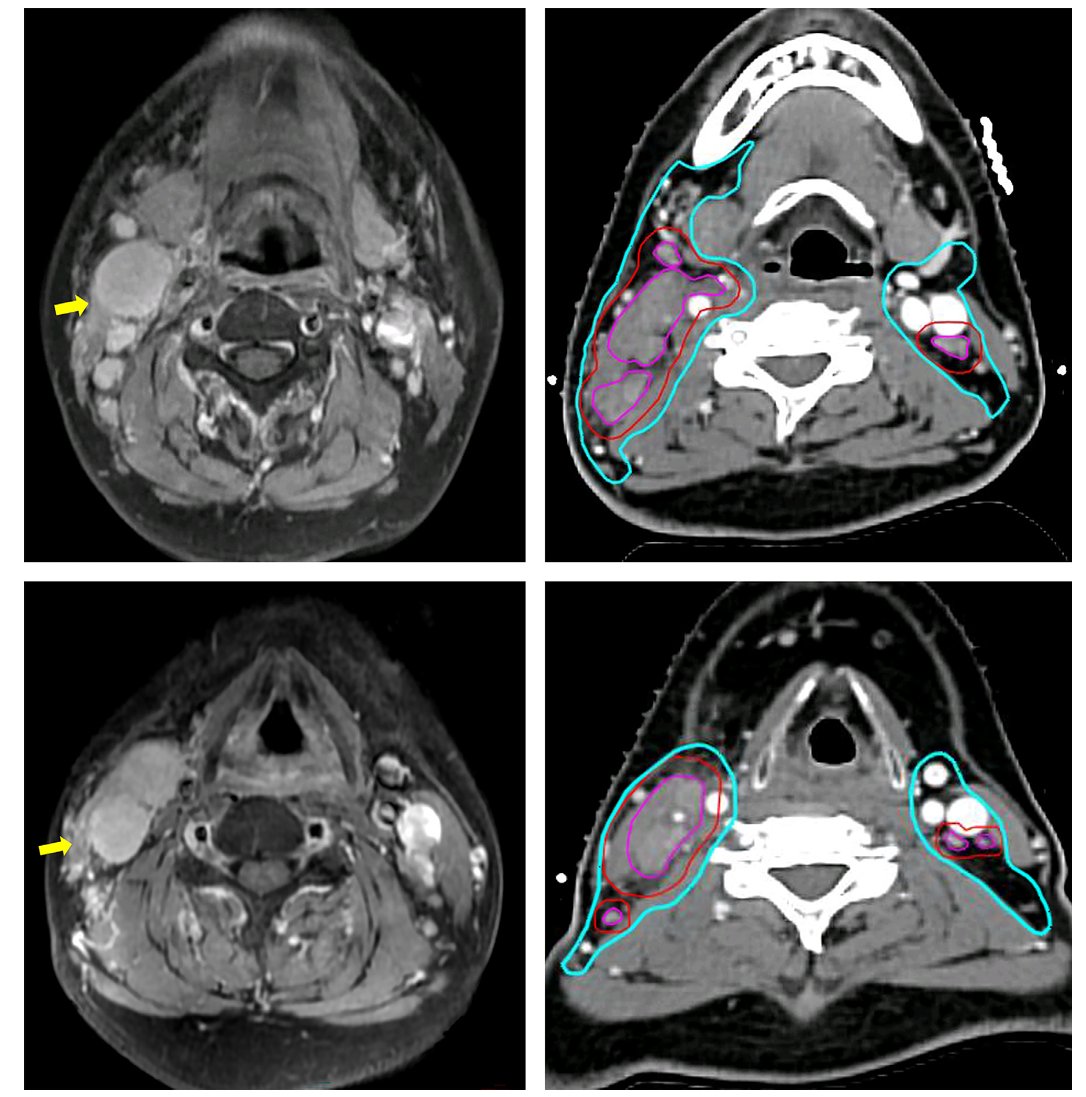

图1 T1偏侧肿瘤原发临床靶区的勾画

- 高危靶区(CTV-GTVp):即肉眼可见的肿瘤区域,处方剂量为70 Gy。关于其外放边界,专家意见存在分歧,因此指南提出了0-5毫米的灵活范围,允许各中心根据自身技术条件进行调整。

- 中危靶区(CTV1):处方剂量统一为60 Gy。其外放边界从过去的10毫米调整为8-10毫米,并强烈推荐将整个鼻咽部纳入此剂量水平的靶区。

- 低危靶区(CTV2):处方剂量为50 Gy。指南强调了“逐步考虑”和“选择性豁免”的理念,特别是对于单侧肿瘤,可以考虑豁免对侧部分结构的照射,以减少不必要的损伤。例如,对侧海绵窦、卵圆孔等区域在特定条件下可被豁免。